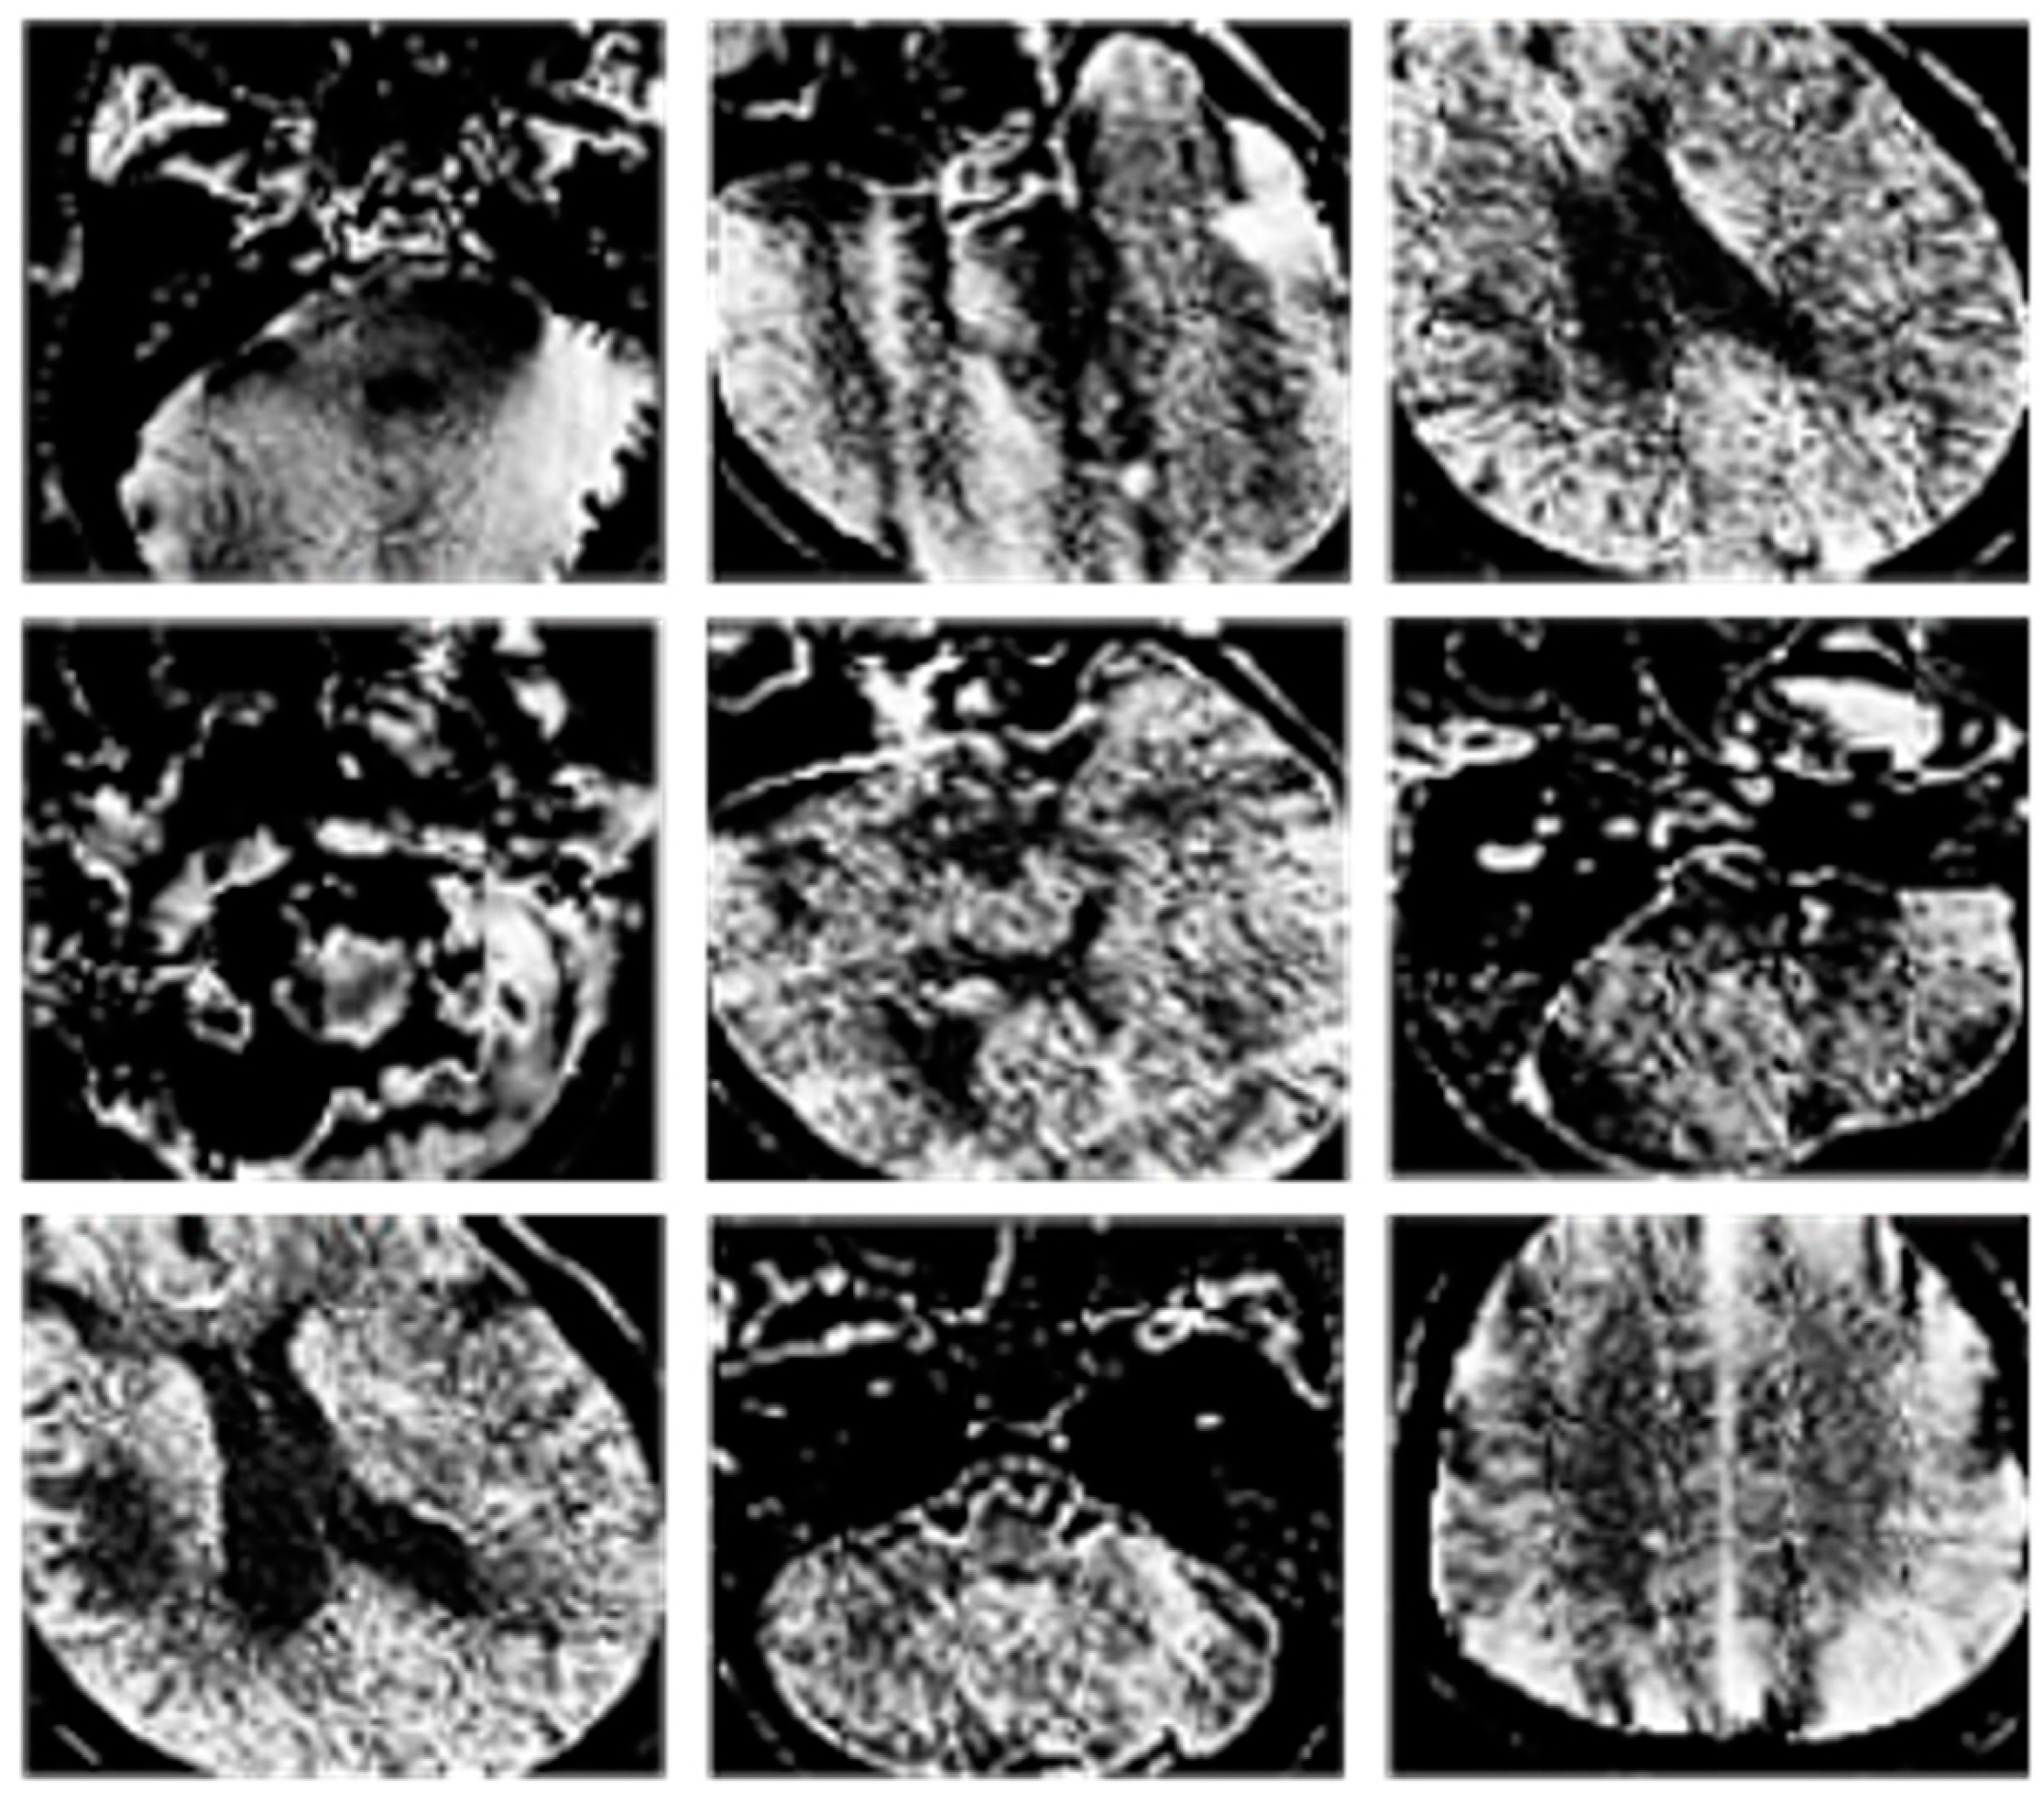

Examples of the classification results are provided in Figure 5 and Figure 6.

Figure 5. Results of CT image classification. In particular, CT images with artifacts.